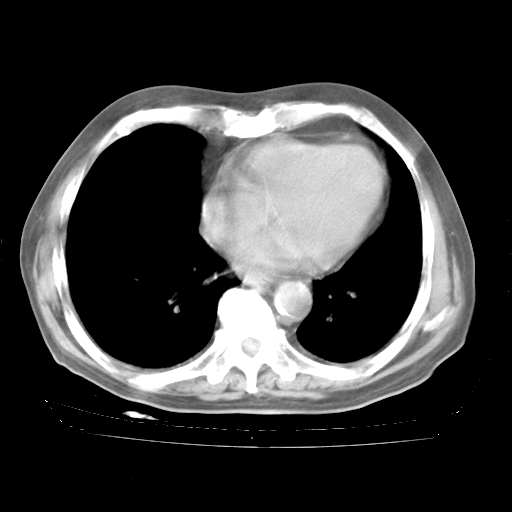

4月28日肺部CT——再次出现类似去年5月9日——透光度降低,“间质性”改变。

4月28日肺部CT——再次出现类似去年5月9日——磨玻璃样、间有“粟粒样”改变。

4月28日肺部CT